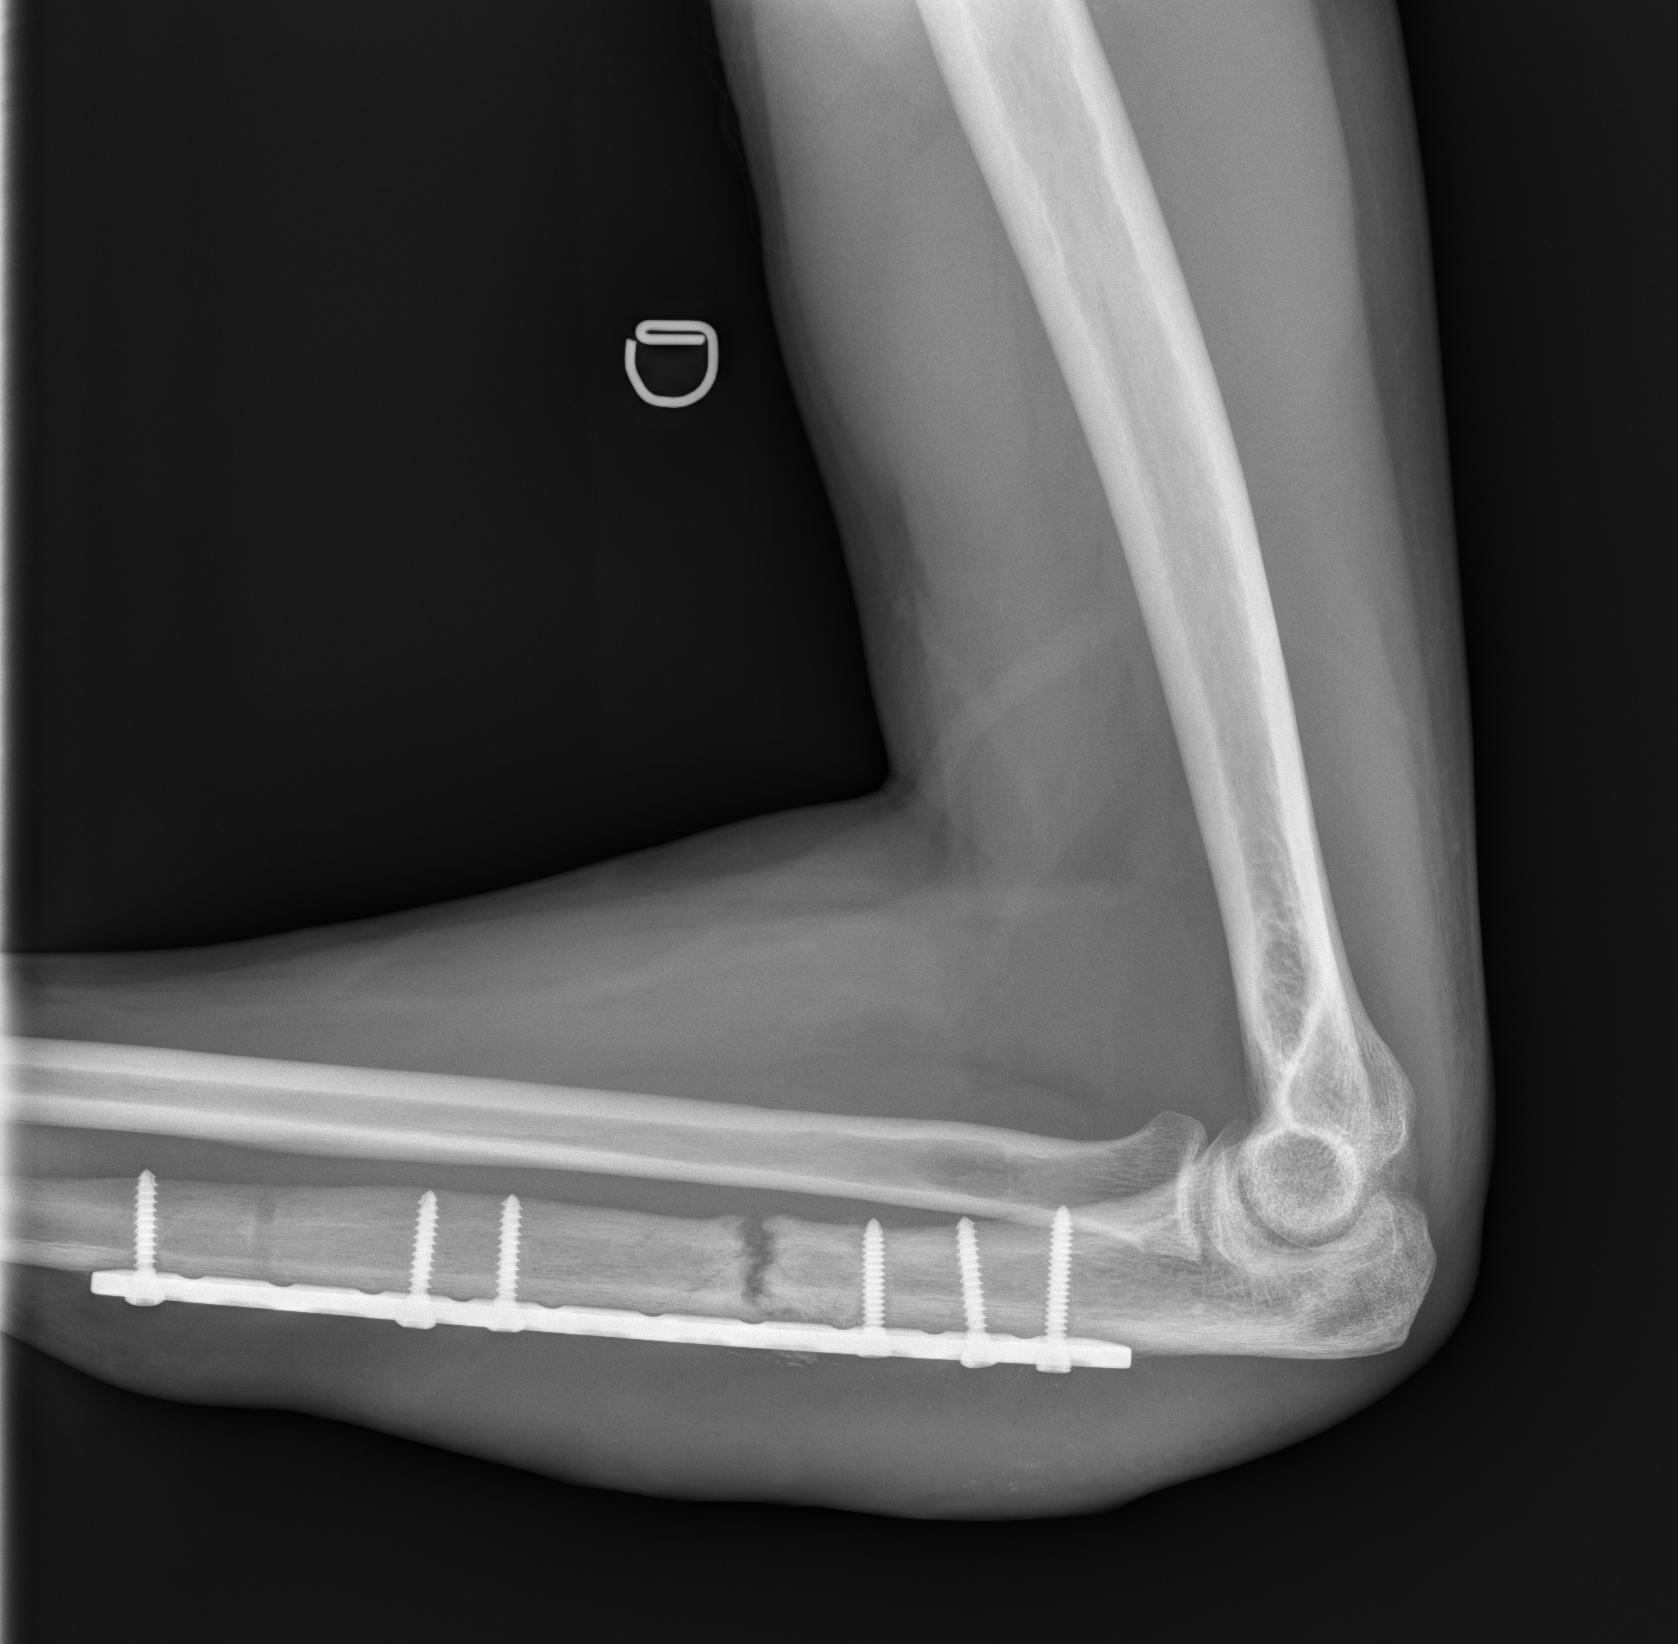

De acuerdo con los datos suministrados por la institución, los huesos de las piernas son los más injertados. En los últimos cinco años, dos de cada cinco (el 41,97%) han sido en los huesos de la pierna, principalmente en la tibia y el peroné, con el 25,81% de todos los injertos.

- Radio y cúbito: 19

Un injerto de hueso es necesario en ciertas condiciones, especialmente cuando hay una pérdida ósea significativa o una curación inadecuada de fracturas. También puede darse debido a enfermedades, como el cáncer o la osteonecrosis (muerte de tejido óseo), en las que el hueso se debilita y no puede dar contención.

Este implante crea una base sólida que le da estabilidad y soporte al cuerpo cuando el hueso original no puede hacerlo.